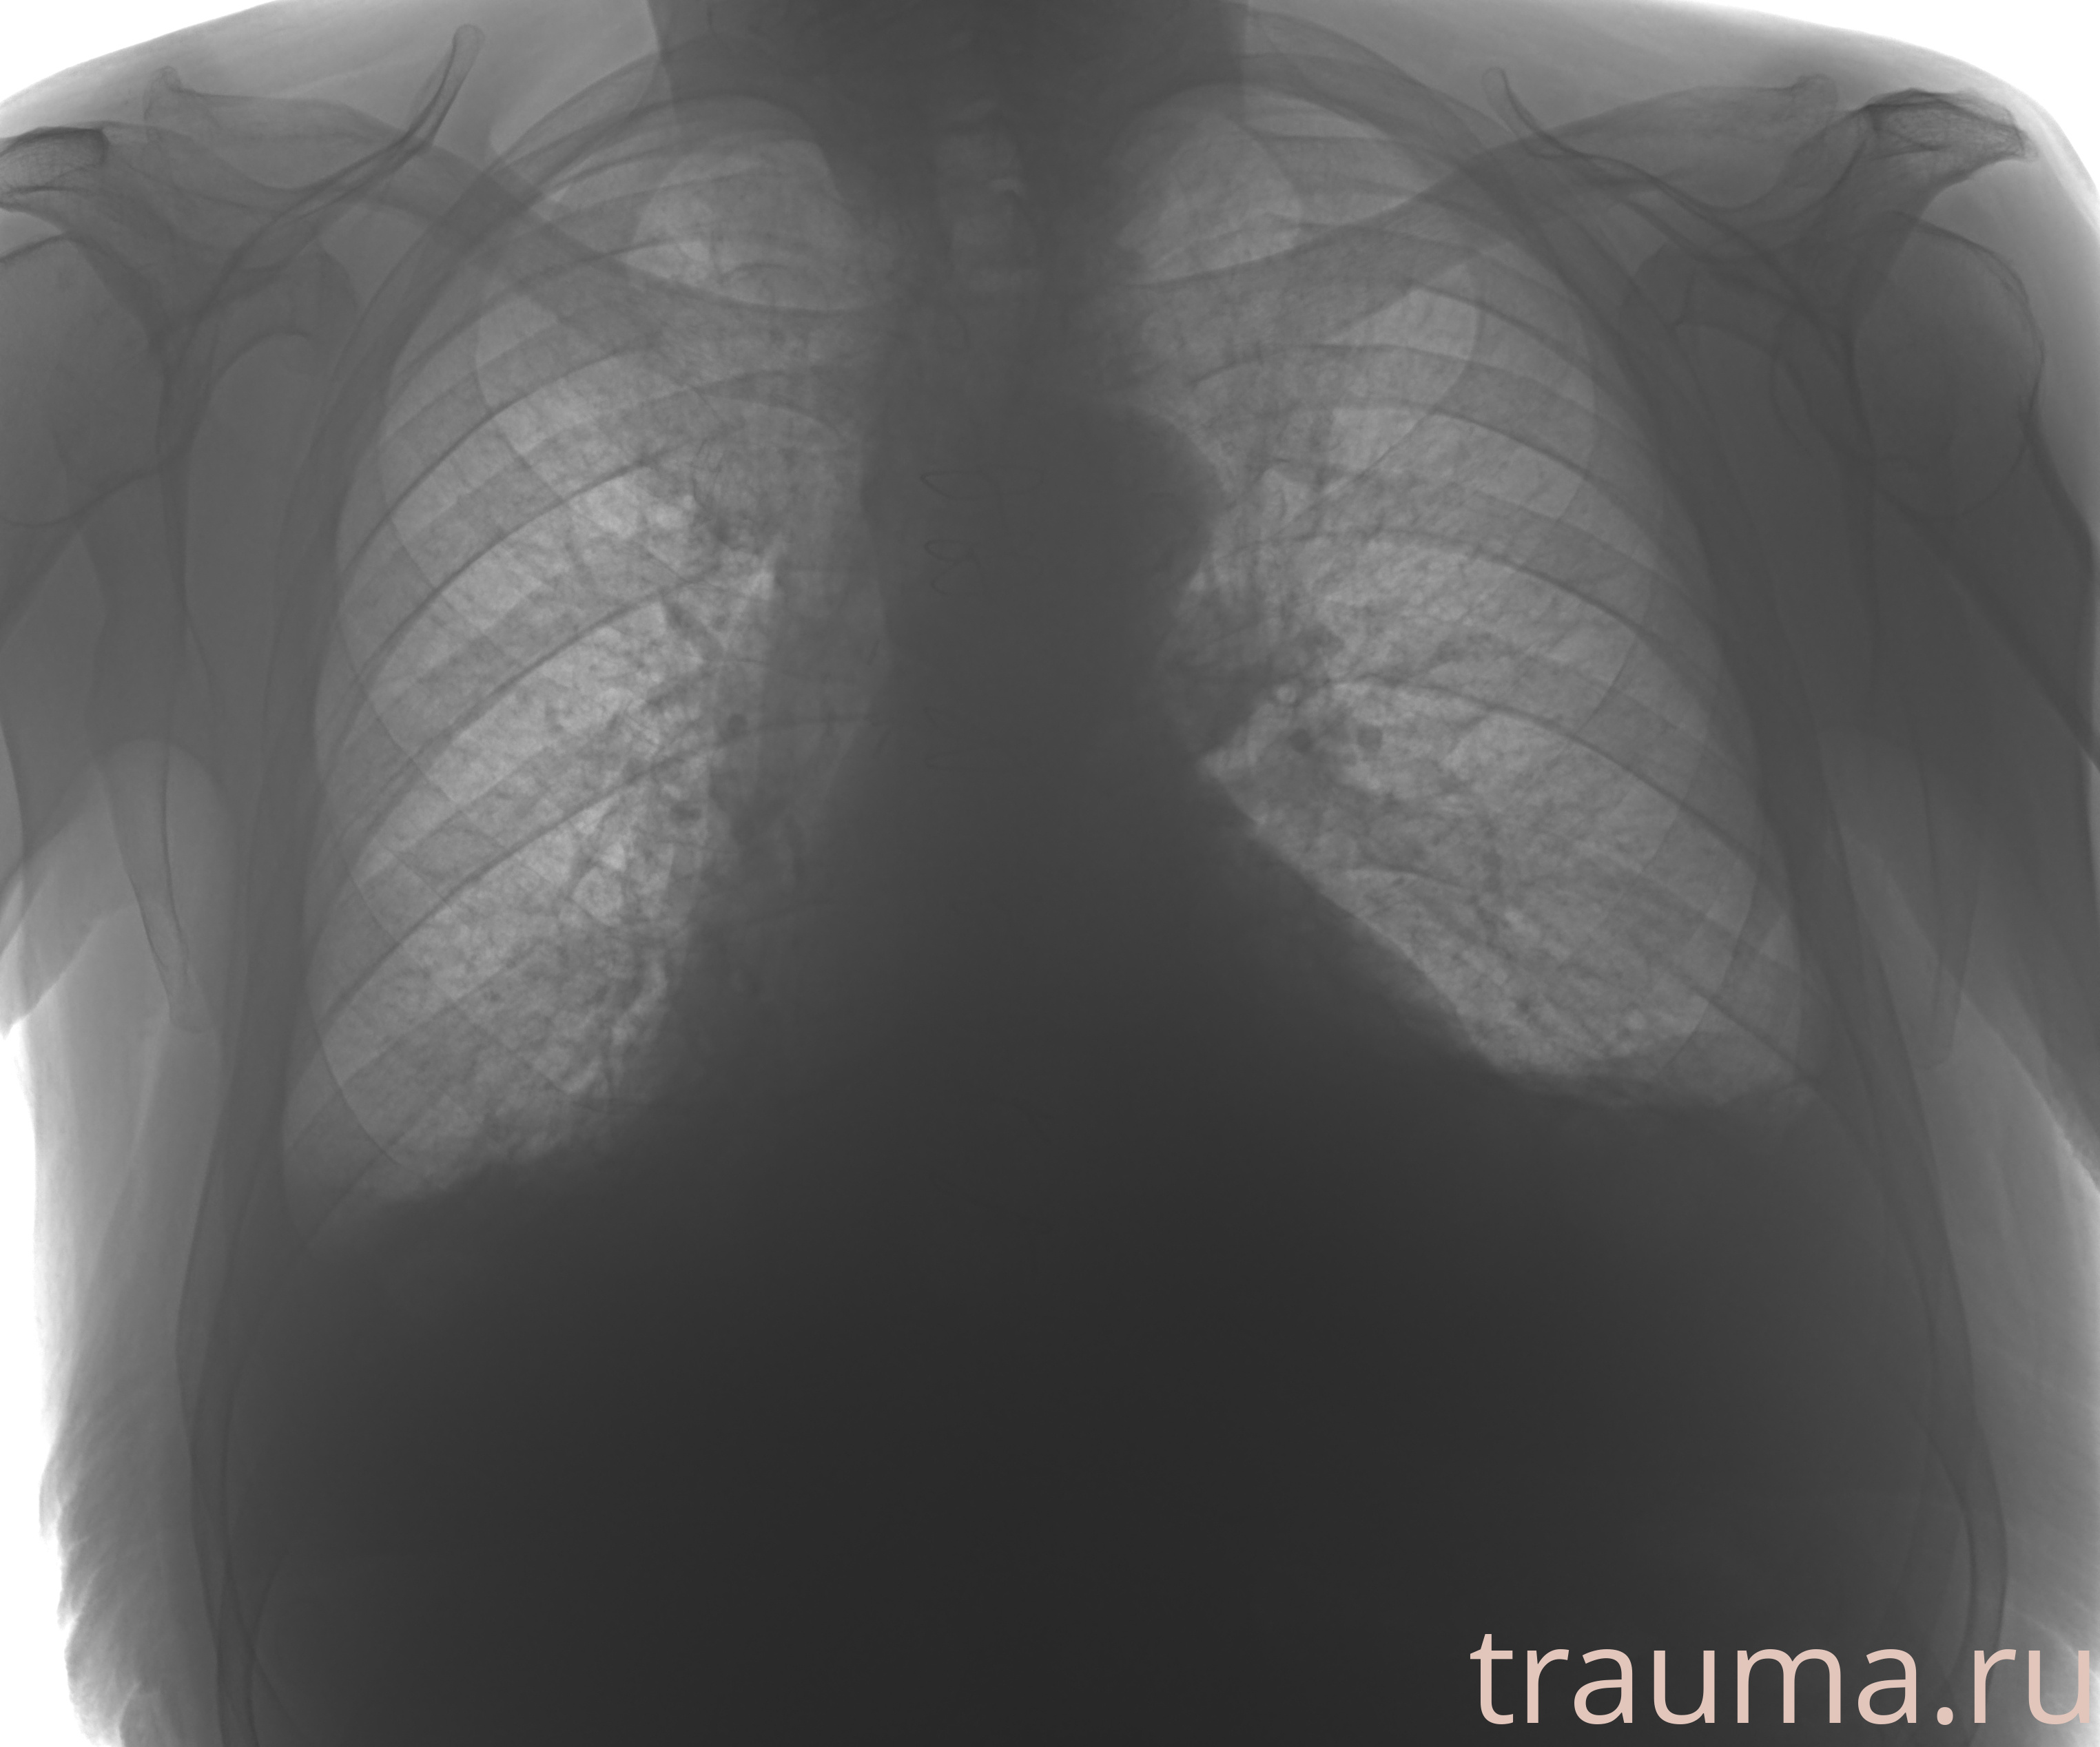

Рентген на дому: по вашему адресу приезжает врач-рентгенолог, травматолог-ортопед с мобильным рентгеновским аппаратом, проводит диагностику травмы или заболевания, делает необходимые рентгенограммы, дает рекомендации по дальнейшему лечению. Получить качественные снимки в домашних условиях возможно благодаря уникальной методике, разработанной МосРентген Центром для института  Склифосовского

при переломе шейки бедра и пневмонии от компании МосРентген Центр - партнера Института имени Склифосовского